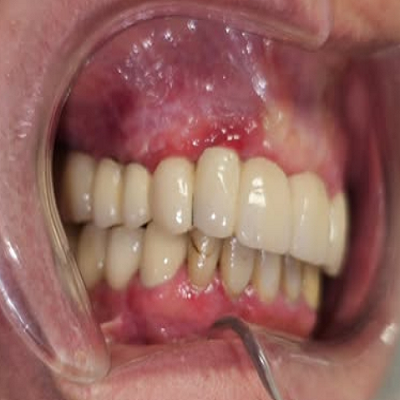

خدمات بهترین جراح فک و صورت در پاسداران

بهترین جراحان فک و صورت در پاسداران خدمات متنوع و تخصصی را برای درمان مشکلات فک و صورت ارائه میدهند. این خدمات شامل:

- جراحی پلاستیک صورت: اصلاح ناهنجاریهای صورت و فک

- جراحی فک و چانه: برای اصلاح مشکلات فکی، جلو یا عقب بودن فک

- ایمپلنت دندان: برای درمان مشکلات فکی و دندان

- جراحی زیبایی بینی: جراحی بینی برای بهبود تناسب صورت

- جراحیهای ترمیمی: شامل درمان شکستگیهای فک و صورت و بازسازی استخوانها

- جوانسازی صورت: شامل لیفت صورت، زاویهسازی فک و استفاده از پروتز گونه

- تزریق ژل و بوتاکس: برای رفع چین و چروکهای صورت و جوانسازی

این جراحان از تکنیکهای پیشرفته و تجهیزات مدرن برای دستیابی به بهترین نتایج استفاده میکنند. انتخاب یک جراح با تجربه در این زمینه میتواند به شما کمک کند تا درمان مؤثر و موفقی داشته باشید.